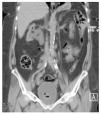

El caso que presentamos es una paciente con infección de vías urinarias complicada en pielonefritis enfisematosa bilateral, secundaria a uropatía obstructiva por la vena ovárica bilateral, por lo anterior tiene la particularidad de estar en el 11% de la presentación general, ya que dentro de los estudios de imagen no se evidenció la presencia de otro proceso obstructivo que condicionara la ureteropielocaliectasia y por consiguiente, el proceso enfisematoso. El cuadro clínico fue muy inespecífico, y la paciente fue ingresada por complicación de una pielonefritis enfisematosa. En la Figura 1, se observa un proceso enfisematoso en el uréter en el tercio proximal derecho. En la Figura 2, se observa ectasia bilateral con gas en parénquima renal en el polo superior derecho y en las cavidades del riñón izquierdo, así como el uréter del mismo lado, también se alcanza a observar la presencia de una escotadura en el uréter superior izquierdo y algo del derecho, justo por debajo de la unión ureteropiélica, que es el lugar donde se cruza con la vena ovárica.

Figura 1. Proceso enfisematoso en uréter tercio proximal derecho (flecha).